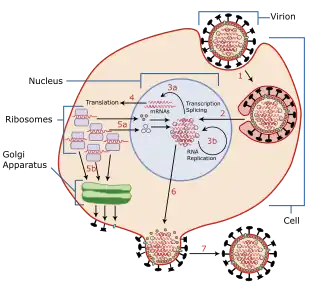

Viruses can replicate only in living cells.[69] Influenza infection and replication is a multi-step process: First, the virus has to bind to and enter the cell, then deliver its genome to a site where it can produce new copies of viral proteins and RNA, assemble these components into new viral particles, and, last, exit the host cell.[60]

Influenza viruses bind through hemagglutinin onto sialic acid sugars on the surfaces of epithelial cells, typically in the nose, throat, and lungs of mammals, and intestines of birds (Stage 1 in infection figure).[70] After the hemagglutinin is cleaved by a protease, the cell imports the virus by endocytosis.[71]

The intracellular details are still being elucidated. It is known that virions converge to the microtubule organizing center, interact with acidic endosomes and finally enter the target endosomes for genome release.[72]

Once inside the cell, the acidic conditions in the endosome cause two events to happen: First, part of the hemagglutinin protein fuses the viral envelope with the vacuole's membrane, then the M2 ion channel allows protons to move through the viral envelope and acidify the core of the virus, which causes the core to disassemble and release the viral RNA and core proteins.[60] The viral RNA (vRNA) molecules, accessory proteins and RNA-dependent RNA polymerase are then released into the cytoplasm (Stage 2).[73] The M2 ion channel is blocked by amantadine drugs, preventing infection.[74]

These core proteins and vRNA form a complex that is transported into the cell nucleus, where the RNA-dependent RNA polymerase begins transcribing complementary positive-sense vRNA (Steps 3a and b).[75] The vRNA either is exported into the cytoplasm and translated (step 4) or remains in the nucleus. Newly synthesized viral proteins are either secreted through the Golgi apparatus onto the cell surface (in the case of neuraminidase and hemagglutinin, step 5b) or transported back into the nucleus to bind vRNA and form new viral genome particles (step 5a). Other viral proteins have multiple actions in the host cell, including degrading cellular mRNA and using the released nucleotides for vRNA synthesis and also inhibiting translation of host-cell mRNAs.[76]

Negative-sense vRNAs that form the genomes of future viruses, RNA-dependent RNA polymerase, and other viral proteins are assembled into a virion. Hemagglutinin and neuraminidase molecules cluster into a bulge in the cell membrane. The vRNA and viral core proteins leave the nucleus and enter this membrane protrusion (step 6). The mature virus buds off from the cell in a sphere of host phospholipid membrane, acquiring hemagglutinin and neuraminidase with this membrane coat (step 7).[77] As before, the viruses adhere to the cell through hemagglutinin; the mature viruses detach once their neuraminidase has cleaved sialic acid residues from the host cell.[70] After the release of new influenza viruses, the host cell dies.